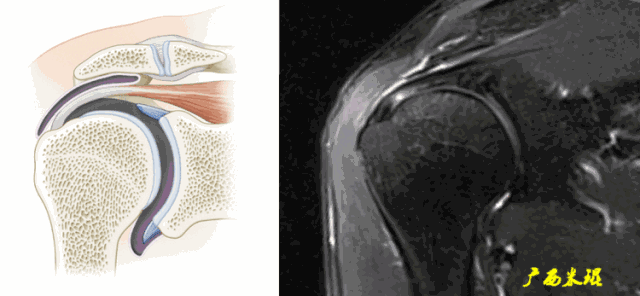

各个序列肩袖均表现为均匀的低信号,是肌腱的延续。

Grade0:肩袖形态正常,连续性完好,肩袖信号正常。

Grade1:肩袖形态正常,连续性完好,肩袖内信号异常。

Grade2:肩袖连续性存在,形态异常(肩袖变薄/变厚,形态不规则)。

Grade3:肩袖外形异常,连续性中断。

在Zlaikin分级中,0级是正常肩袖,1、2级代表退变,3级为撕裂,也就是真正的肩袖损伤。